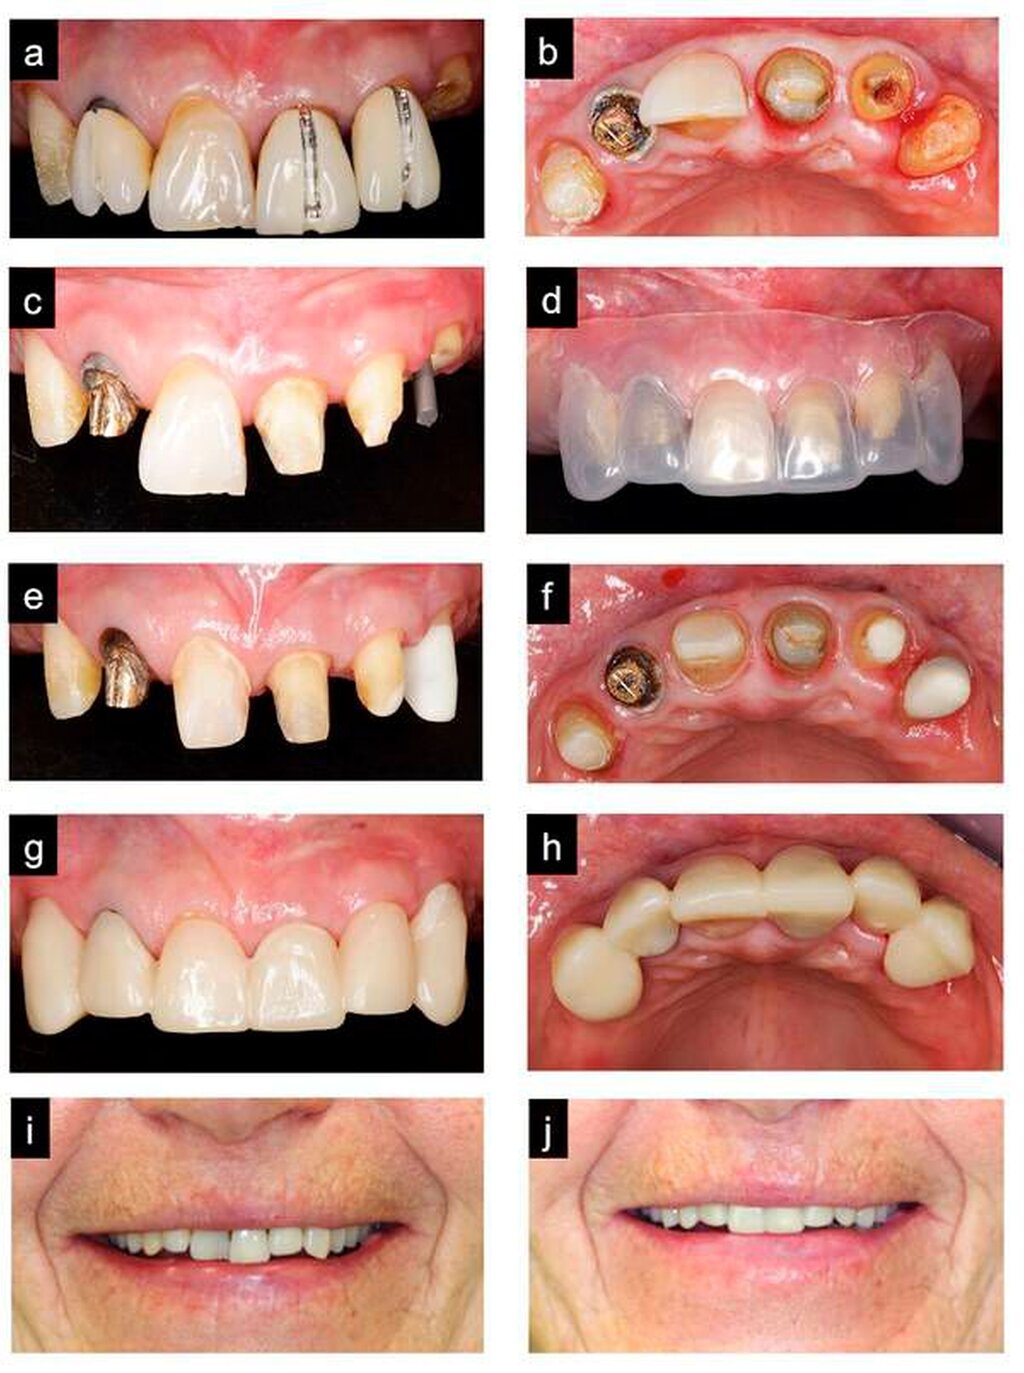

Die Abbildungen 5a bis 5j zeigen den detaillierten Ablauf des folgenden Behandlungsabschnitts, nämlich die Entfernung der Frontkronen, den direkten plastischen Stiftaufbau an Zahn 23 mit einem Titanstift (ER-System, Komet, Deutschland) und einem dualhärtenden Komposit für Stumpfaufbauten (Luxacore Z, DMG, Deutschland), die Vorpräparation an allen Zähnen und die provisorische Versorgung. Eine minimalinvasive, weitestmöglich schmelz-begrenzte Präparation erfolgte an Zahn 11 für die spätere Aufnahme eines Full Veneers.

In den Abbildungen 5i bis 5j ist eine deutliche Harmonisierung der ästhetischen Erscheinung zwischen dem Zustand vor und nach Versorgung mit dem Provisorium anhand des idealisierten Wax-ups zu erkennen.

Nach Abschluss aller Vorbehandlungsmaßnahmen und der Einhaltung der notwendigen Heilungszeiten nach den erfolgten perioprothetischen, chirurgischen Eingriffen konnte nun die prothetische Phase beginnen, die das Nachpräparieren der Zähne, die definitive Abformung der Zähne und Implantate, die professionelle Farbbestimmung, die Kieferrelationsbestimmung, die Abutment-, Gerüst-, Rohbrand- und Ästhetikanprobe(n) und die Fertigstellung des Zahnersatzes beinhaltete (Abbildungen 7a bis 7h).

In der ästhetischen Zone der Oberkieferfront wurden an Zahn 11 ein individuell verblendetes Full Veneer auf Basis eines Lithiumdisilikatkeramikgerüsts und an den übrigen Zähnen in regio 13–23 vollkeramische, vollverblendete Kronen auf Basis eines Zirkoniumdioxidgerüsts angefertigt. Bei den Versorgungen im Seitenzahnbereich wurden vollverblendete, metallkeramische Versorgungen mit feinem Metallrand verwendet, lediglich an 37 wurde eine monolithische Teilkrone aus Lithiumdisilikatkeramik angefertigt. Die Implantatbrücken wurden aufgrund von ungünstigen Implantatangulationen, die keine okklusale Verschraubung ermöglichten, zementiert. Aufgrund der geringen Lachhöhe im Oberkiefer-Seitenzahnbereich konnten hier die Präparationsränder der Abutments epigingival gelegt werden und waren somit gut von Zementüberschüssen zu reinigen. Es wurde auf eine reinigbare Konstruktion des Zahnersatzes geachtet. Als Okklusionskonzept wurde eine Front-Eckzahn-geschützte Okklusion realisiert (Abbildungen 8a bis 8f).